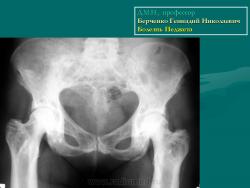

Доктор медицинских наук, профессор   Берченко Геннадий Николаевич

Болезнь Педжета проявляется у больных в возрасте старше 40 лет. Заболеваемость варьирует в пределах 0,1–3% населения. У лиц моложе 40 лет частота заболеваемости не превышает 0,5%, у лиц старше 90 лет частота заболеваемости около 10%. Деформирующий остоз чаще встречается у мужчин. Поражение только одной кости (монооссальная форма), преимущественно большеберцовой, бедренной, или таза встречается редко, в 85% в процесс вовлекается множество костей (длинные кости, кости таза, черепа и позвоночника) ― полиоссальная форма. В основном поражаются кости, несущие наибольшую механическую нагрузку (поясничные и крестцовые позвонки, бедренная и большеберцовые кости и др.); характерны поражения костей крыши черепа; из лицевых костей чаще поражаются челюсти.

Деформирующая остеодистрофия (болезнь Педжета) чаще проявляется у мужчин в возрасте 40-60 лет, характеризуется постепенно прогрессирующим утолщением коркового слоя костей с развитием гиперостозов, деформацией, искривлением костей, беспорядочностью их структуры, образованием в них кист; поражаются кости мозгового черепа, позвоночника и длинных трубча­тых костей. Размеры мозгового черепа увеличиваются, наружная пластинка костей свода черепа местами утолщена, гиперостозы чередуются с участка­ми беспорядочного разрежения кости. В связи с деформацией костных от­верстий и каналов основания черепа и межпозвонковых отверстий наруша­ется функция черепных и спинномозговых нервов, возможны расстройства кровообращения. Деформация глазниц обусловливает экзофтальм. Нередко отмечаются признаки внутричерепной гипертензии. Позвонки сплющены; в трубчатых костях сужены костномозговые каналы, возможны патологические переломы костей, при этом линия перелома четкая, ровная, как при переломе очищенного банана («банановый перелом»); усилены физиологические изгибы позвоночника. Процесс может быть относительно ограниченным или распро­страненным. Содержание кальция и фосфора в крови нормально или слегка увеличено, активность щелочной фосфатазы повышена. Предполагается доми­нантный тип наследования с различной экспрессивностью. Описал болезнь в 1877 г. английский хирург J. Paget (1814-1899).